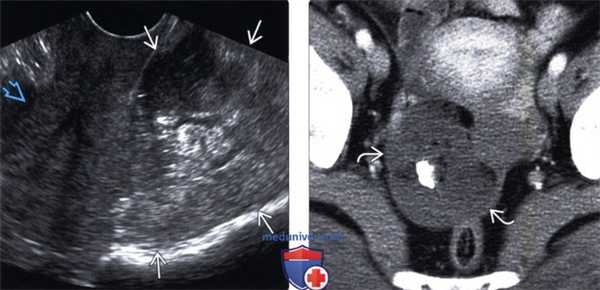

(Слева) Трансвагинальная ультрасонография: отмечается, что дермоид может иметь нехарактерную картину визуализации на ультрасонографии при условии, что мягкотканный компонент будет преобладать над жировым. Данный дермоид гетерогенно эхогенный и заполняет замкнутое пространство кзади от матки.

(Справа) КТ с контрастированием того же образования, аксиальный срез: определяется относительно небольшое количество жира с преимущественно мягкотканным компонентом, что формирует специфичную картину визуализации на ультрасонографии.